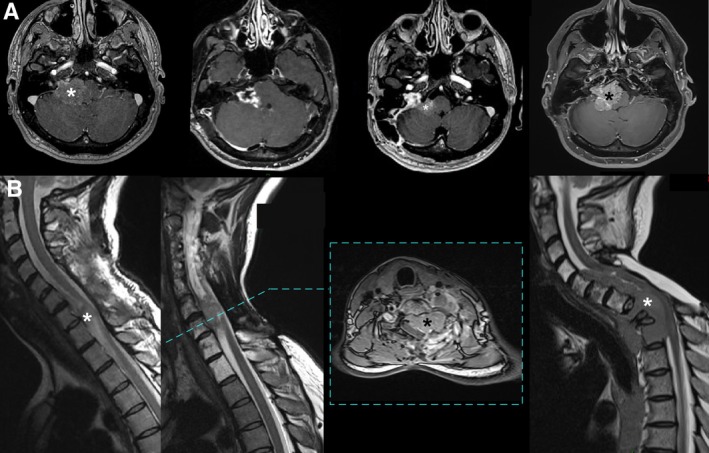

bap1缺失型脑膜瘤优先定位于幕下或脊柱,可能表现为小细胞或上皮样细胞的未分化组织学,而不是脑膜上皮、横纹肌或乳头状变异。细胞角蛋白的频繁表达可能会误导转移性癌,但肿瘤细胞中BAP1免疫染色的缺失和特定的甲基化分类使诊断成为可能。BAP1缺陷脑膜瘤的组织分子诊断的临床影响是复发的高风险和可能潜在的BAP1肿瘤易感综合征。

BAP1-deficient meningiomas have a preferential infratentorial or spinal localization and may present with an undifferentiated histology of small or epithelioid cells rather than the meningothelial, rhabdoid or papillary variants. Frequent expression of cytokeratins may be misleading for a metastatic carcinoma but loss of BAP1 immunostaining in tumor cells and a specific methylation class enable the diagnosis. The clinical impact of the histomolecular diagnosis of BAP1-deficient meningioma is the high risk of relapse and a possible underlying BAP1 tumour predisposition syndrome.